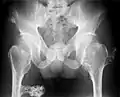

múltiples osteocondromas en la pelvis -